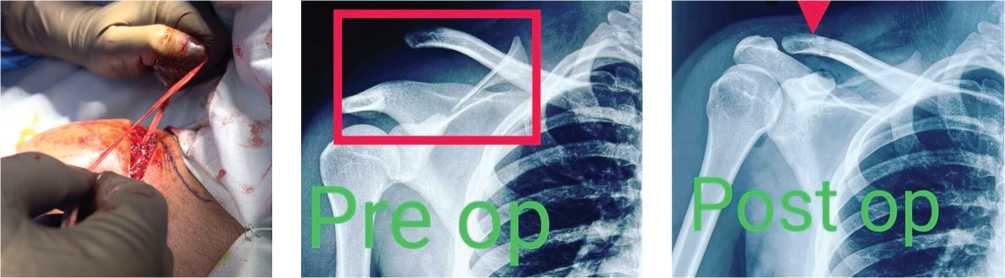

Fig. 8. Pre-op X-ray

Fig. 9. Post-op X-ray

The mean (SD) UCLA score increased from 29.20 (1.68) (range 30–35) at three months to a maximum of 35.00 at the six-month review. The improvement in the UCLA score at six months was statistically significant (Wilcoxon test: V = 0.0, P = 0.001). Radiological evaluation confirmed 100 % reduction and congruence among the participants.

In our study, the radiological evaluation during follow-up confirmed 100 % reduction and convergence at six months. No donor site morbidity was reported. However, DVT was observed in one patient that was managed conservatively.